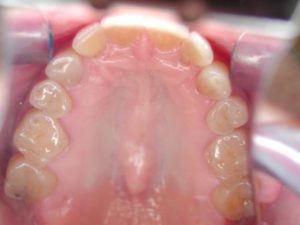

She knew she had wear on her teeth from grinding. After showing her images of her individual teeth, she realized the extent of the damage more clearly.

She asked for options. Little did any of us know that she would decide to obtain a smile makeover to correct the tooth damage and to enhance her smile.